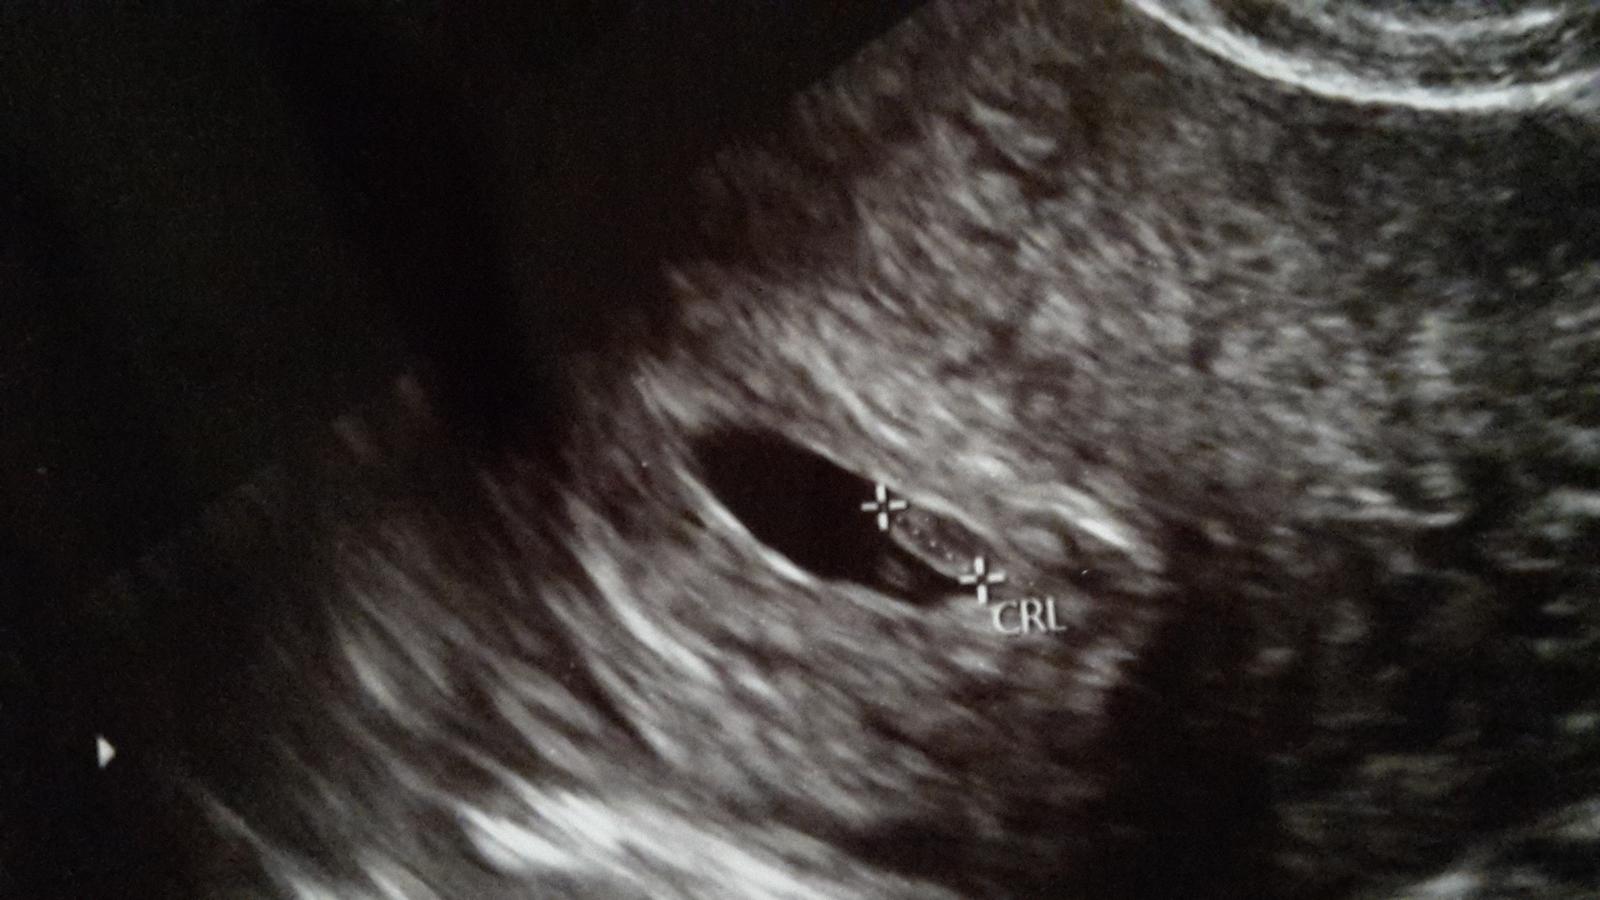

Podľa kalkulačky sme 6+1tt a 7.9. sme boli na kontrole u gyn a ten videl len gestačný vačok. Myslíte, že máme mať obavy? Na kontrolu ideme 14.9., ale veľmi sa bojíme, že tam žiadna fazuľka nebude. Mali Ste nejaká z Vás takúto skúsenosť?

@bubu1983 Ahoj. Ja som pomerne kľudná, aj keď na to tiež stále myslím.. Ja som dnes 6tt +3 a dnes večer ideme k dr, tak som zvedavá.. Dúfam, že už bude vidno aj bábatko a aj srdiečko a všetko bude v poriadku. Naposledy pred týždňom bolo vidieť iba gestačný vak a žlté teliesko. Ešte som zvedavá, či bude bábo jedno alebo dve 😀 Mala som dosť vysoké HCG a obaja s manželom máme v rodine dvojičky, tak som veľmi zvedavá, čo dnes uvidíme.. Už začínam byť trošku nervózna z toho..